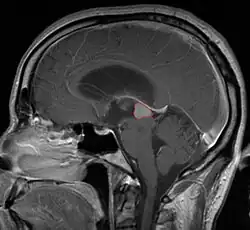

Radiation Oncology/CNS/Pineal

Pineal Gland Tumors

Clinical Presentation

• Determined by the spatial anatomy and direction of growth

• Obstruction of aquaduct: hydrocephalus presenting as headaches, nausea, vomiting

• Compromise of superior colliculus: vertical gaze palsy, pupillary and oculomotor nerve paresis (Parinaud syndrome)

• Work-up includes MRI, CSF, serum markers for bHCG and AFP

• Tissue diagnosis is critical, since management varies significantly based on pathology